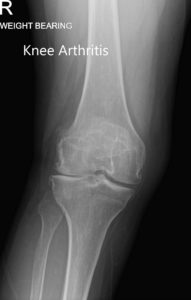

Her physical examination revealed mild swelling in the right knee with no erythema or rise of temperature. There was a medial joint line and medial patellar facet tenderness. The range of motion was full with no deformity. There was no distal neurological deficit. The examination of her bilateral ankles and knees was unremarkable. Her imaging studies revealed severe tricompartmental osteoarthritis of the right knee.

Preoperative weight-bearing X-ray showing AP and lateral views of the right knee